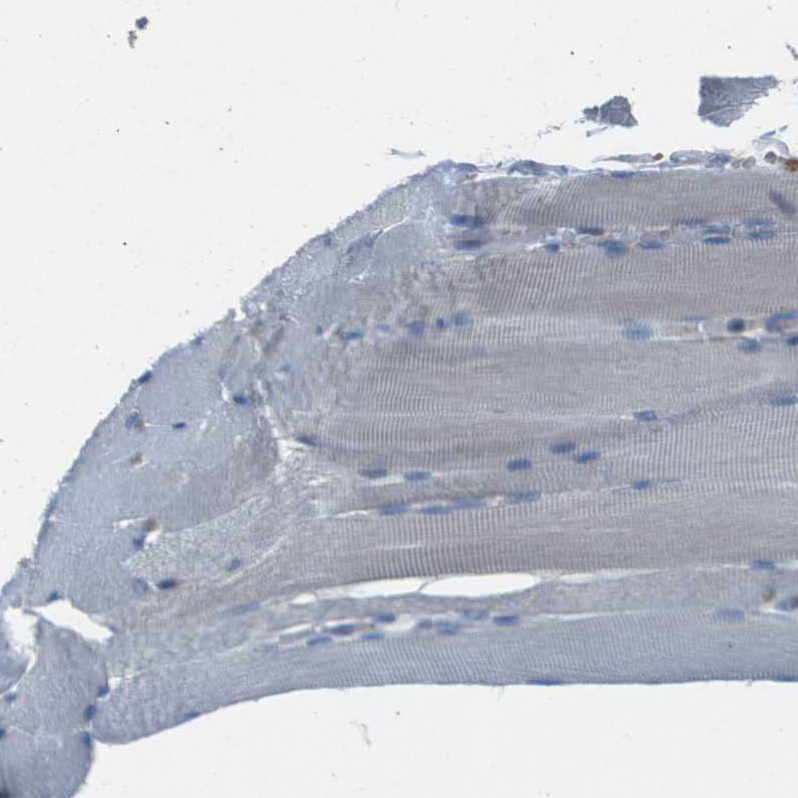

Immunohistochemical staining of human cerebral cortex shows moderate nuclear positivity in neurons.